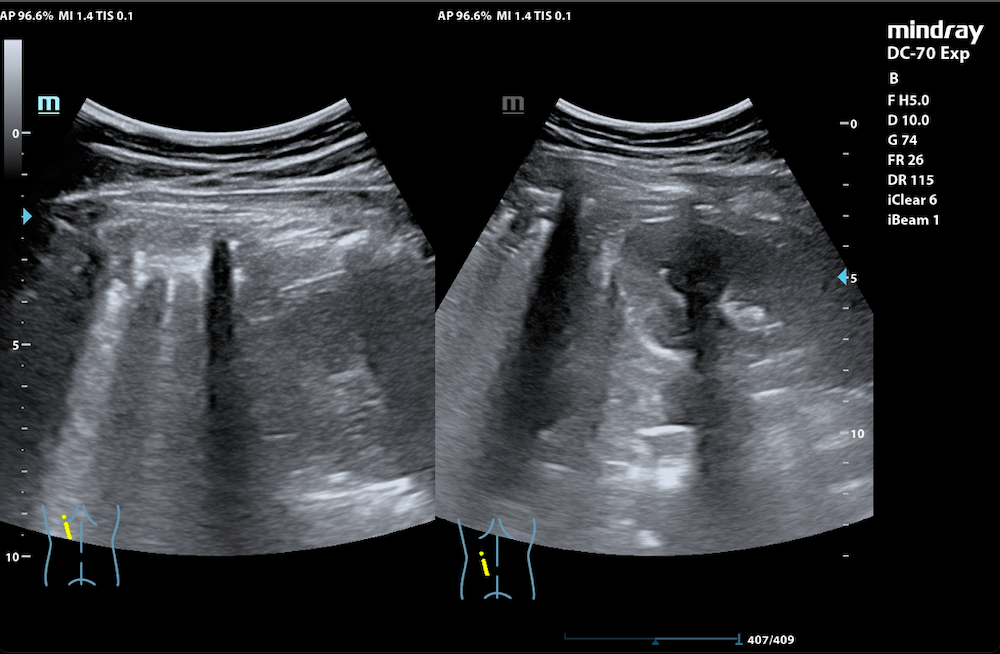

Paciente de 15 años con AP de asma y rinitis alérgica que acude al Servicio de Urgencias por fiebre de hasta 38,5 ºC y tos seca de 2 días de evolución. Además, refería dolor abdominal en hipocondrio izquierdo sin cambios en el hábito intestinal y sin vómitos. Dada la estabilidad del paciente y exploración física anodina se decide tratamiento sintomático en domicilio y revisión en consulta en días posteriores. Acude a la consulta tres días después refiriendo persistencia de la fiebre, disminución parcial de la ingesta y aumento de frecuencia de los accesos de tos seca. Exploramos al paciente: presenta crepitantes bibasales junto a algún roncus acentuado en base izquierda, se solicita una radiografía de tórax donde se objetiva una consolidación incipiente en la base pulmonar izquierda que borra mínimamente el reborde superior diafragmático. Debido a la alta incidencia de casos y clínica atípica compatible con infección por Mycoplasma se realiza un exudado resultando ser positivo, por lo que se pauta antibioterapia con Azitromicina durante 3 días. Tras haber cumplido con la pauta medicamentosa, acude nuevamente a consulta refiriendo picos febriles de hasta 40 ºC, malestar general, tos con expectoración y empeoramiento del dolor abdominal. Dado que a la auscultación y clínica presenta empeoramiento decidimos realizar una ecografía pulmonar para descartar complicaciones: se objetiva consolidación de ecogenicidad variable en su interior localizado en base pulmonar izquierda, con presencia de líneas B en el parénquima pulmonar sin presentar aparente derrame pleural.

Gracias a la ecografía se ha podido diagnosticar lo anterior sin irradiar nuevamente al paciente.

La ecografía pulmonar ha demostrado una alta precisión para el diagnóstico de neumonía siendo una prueba complementaria que no irradia al paciente. Podemos comenzar a implementarla tanto en la consulta como en los Servicios de Urgencias ofreciendo una respuesta inmediata a la pregunta asistencial y de esta manera, aumentar la capacidad resolutiva y diagnóstica de nuestros pacientes.